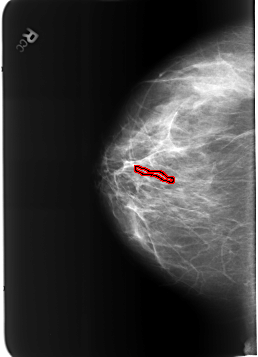

B_3212_1.RIGHT_CC

FILE: B_3212_1.RIGHT_CC.OVERLAY

TOTAL_ABNORMALITIES 1

ABNORMALITY 1

LESION_TYPE CALCIFICATION TYPE VASCULAR DISTRIBUTION N/A

ASSESSMENT 2

SUBTLETY 3

PATHOLOGY BENIGN_WITHOUT_CALLBACK

TOTAL_OUTLINES 1

BOUNDARY